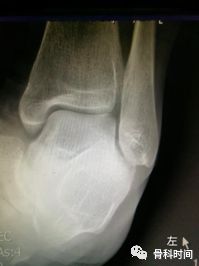

生活中,崴脚后常常忽视外固定的作用,特别是未存在撕脱骨折以及 X 线片假阳性者,踝关节应力位 X 片对于单纯的韧带损伤可发现踝关节不稳。

距骨倾斜角:内翻应力正位片中距骨相对于胫骨远端关节面倾斜角度≥9°,即可考虑踝关节不稳,但此时应考虑患者的职业,如芭蕾舞演员可存在足踝部韧带松弛

30 岁青年女性,1 年前右踝首次发生崴脚,未行外固定,伤后右踝间断数次崴脚,双侧踝关节应力正位片测量距骨倾斜角,左侧为 0°,右侧 7°,右侧虽尚不能诊断踝关节不稳,但距骨倾斜角增大,对比对侧仍考虑为崴脚后未外固定所致。